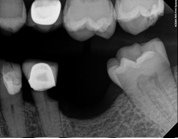

Conventional Treatment with Standard Core Restoration

Non-surgical endodontic treatment with resin core build up